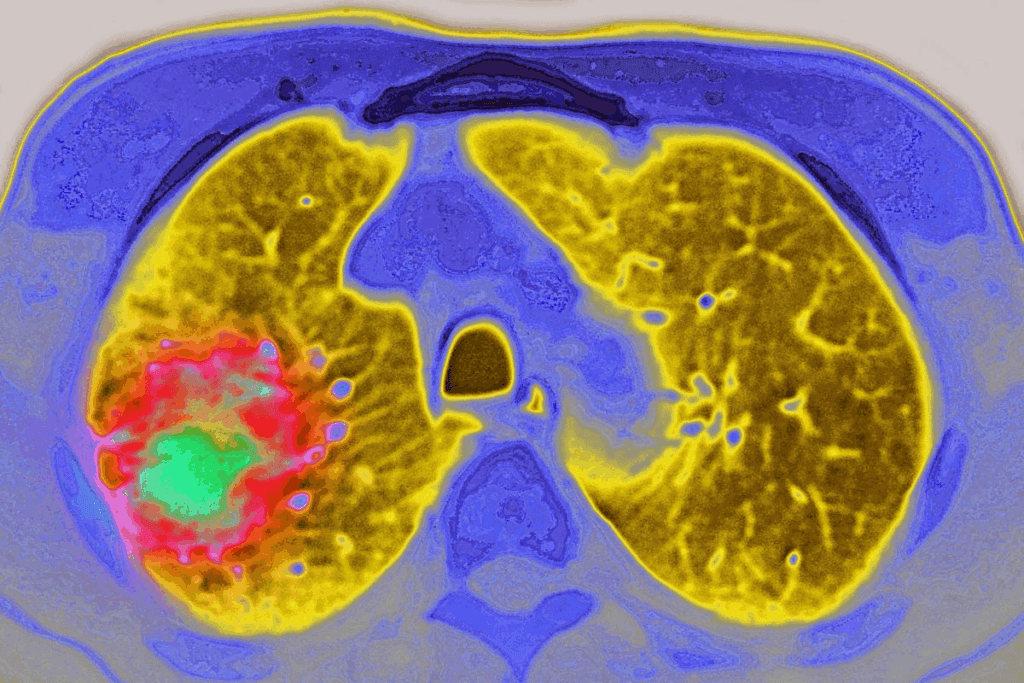

CT-guided biopsy is a new way to get tissue samples for medical tests. It uses CT scans to guide a needle into the right spot. This makes sure the samples are accurate.

A CT scan biopsy, or CT-guided needle biopsy, uses CT scans to guide the needle. It helps get tissue or fluid samples from hard-to-reach places in the body. This is great for diagnosing problems in organs or tissues.

The CT scanner shows real-time images. This helps doctors place the needle exactly where it needs to be.

CT-guided biopsy is used for many health issues. It’s good for checking on lung, liver, kidney, and lymph node problems. It helps find cancers, infections, and inflammatory diseases.

- Diagnosing lung nodules or masses

- Sampling liver or kidney lesions

- Examining lymph node abnormalities

- Investigating suspicious masses or tumors